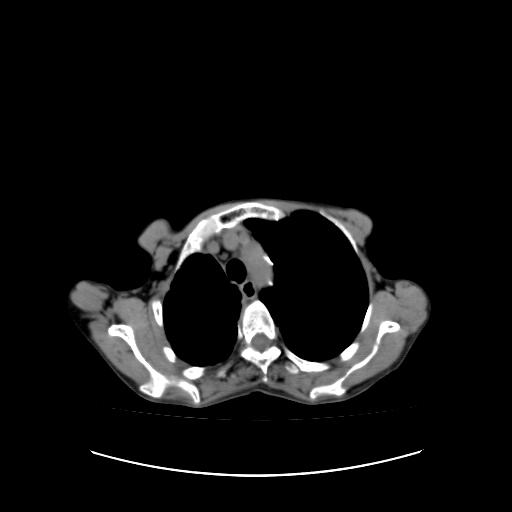

可见多发肺内病灶,且胸膜病灶较多有圆球状而非丘状,多考虑胸膜转移瘤伴胸腔积液,右侧胸廓缩小固定,且部分病灶呈丘状,尚不除外恶性胸膜间皮瘤伴肺内转移

右侧胸膜增厚,局部呈结节状增厚,右侧胸腔少量积液。双肺未见确切肿块影。纵隔未见淋巴结肿大。气管、支气管通畅。考虑右侧胸膜间皮瘤(恶性?)可能性大。不除外癌性胸膜炎。

右侧胸廓塌陷,右侧胸膜广泛增厚并见多发胸膜结节,右侧少量胸腔积液并包裹。

右侧广泛胸膜增厚,局部呈结节状增厚,右侧胸腔少量积液。双肺未见确切肿块影。纵隔未见淋巴结肿大。气管、支气管通畅。考虑右侧胸膜间皮瘤(恶性?)可能性大。支持!